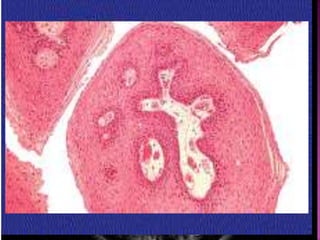

 Histology:

slow replacement of medullary bone by abnormal

fibrous tissue with different stages of bone

metaplasia